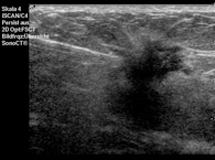

Die Stanzbiopsie erfolgt unter Ultraschallsicht. Nach Desinfektion werden die Haut und der Weg zum auffälligen Befund mit einer feinen Nadel betäubt. Anschließend wird über einen kleinen Hautschnitt eine Punktionsnadel eingeführt und bis an den Befund herangebracht. Durch Auslösen eines Federmechanismus durchsticht die Punktionsnadel den Herdbefund und schneidet dabei ein kleines Gewebestück heraus. Üblicherweise werden zwischen 3 bis 5 Gewebestücke aus unterschiedlichen Arealen eines Herdbefundes entnommen. Die gewonnenen Gewebeproben werden anschließend zur histologischen Begutachtung in die Pathologie übersandt. Die Stanzbiopsie eines Befundes nimmt etwa 20 bis 30 Minuten in Anspruch. Komplikationen, wie Blutergüsse oder eine Entzündung sind insgesamt selten und gut therapierbar.